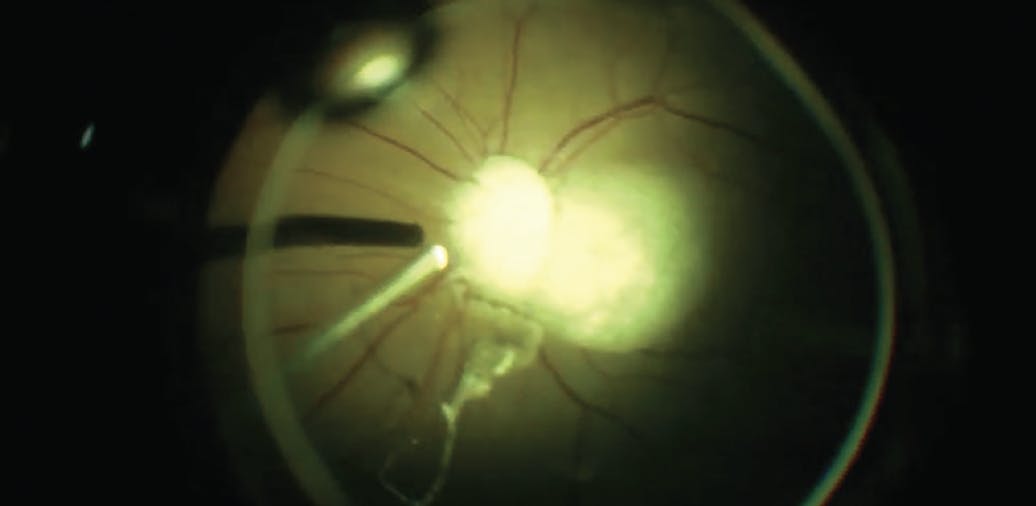

<p>Figure 1. A preoperative OCT of the patient’s right eye demonstrating a small FTMH (A). At 1 week postoperative, the OCT showed an intensely bright outer retinal hyperreflective lesion corresponding to TA particles on the fovea (B). The TA particle is smaller on OCT at week 3 postoperative with residual subretinal fluid (C). At month 2 postoperative, the TA residue is fully absorbed and the subretinal fluid is reduced significantly (D).</p>

Figure 1. A preoperative OCT of the patient’s right eye demonstrating a small FTMH (A). At 1 week postoperative, the OCT showed an intensely bright outer retinal hyperreflective lesion corresponding to TA particles on the fovea (B). The TA particle is smaller on OCT at week 3 postoperative with residual subretinal fluid (C). At month 2 postoperative, the TA residue is fully absorbed and the subretinal fluid is reduced significantly (D).

At postoperative week 1, the gas fill was 40%, and a small but highly reflective TA crystal was seen clinically and on OCT (Figure 1B). At 3 weeks postoperative, the patient noted a small central scotoma in the right eye, and the crystal particle was still visible as a hyperreflective outer retinal lesion on OCT imaging with a small amount of residual subretinal fluid (Figure 1C).

By 2 months postoperative, the TA residue had absorbed, but a small residual amount of subretinal fluid remained (Figure 1D). This patient’s final VA improved to 20/30+1, and he no longer noted a scotoma in the right eye. Fundus autofluorescence did not show any evidence of RPE changes in the macula at 2 months follow-up.